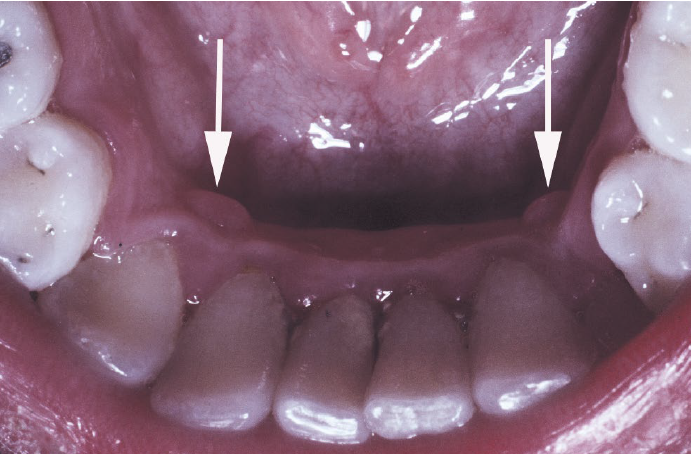

restrocuspid papillae

a normal anatomic variation

on the gingiva lingual to the mandibular cuspid, frequently bilateral

microscopically like giant cell fibroma

no need for treatment